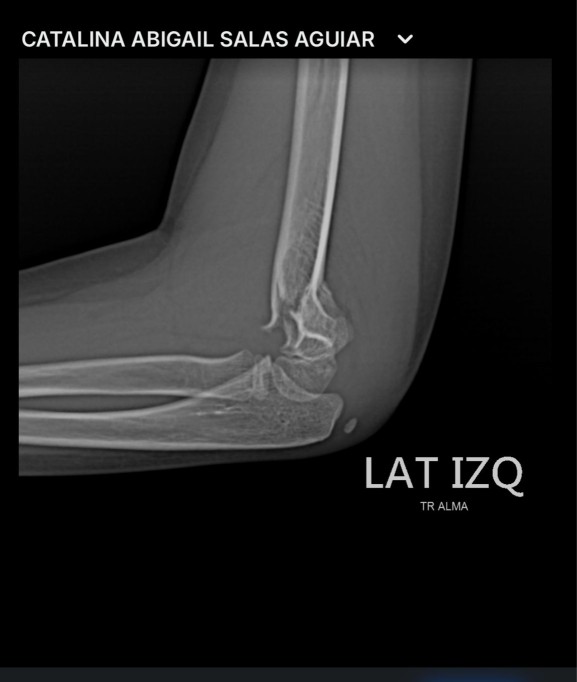

Su hijo tuvo fisura, por lo que fue necesaria una intervención quirúrgica con la colocación de tres clavos en la parte lesionada. Estará hospitalizada hasta su recuperación, por lo que Isidro y su familia pusieron en la Fiscalía General de Yucatán una denuncia para alertar a padres de familia que este lugar, a pesar de ser un establecimiento de diversión extrema, no cuenta con personal calificado, material y primeros auxilios.